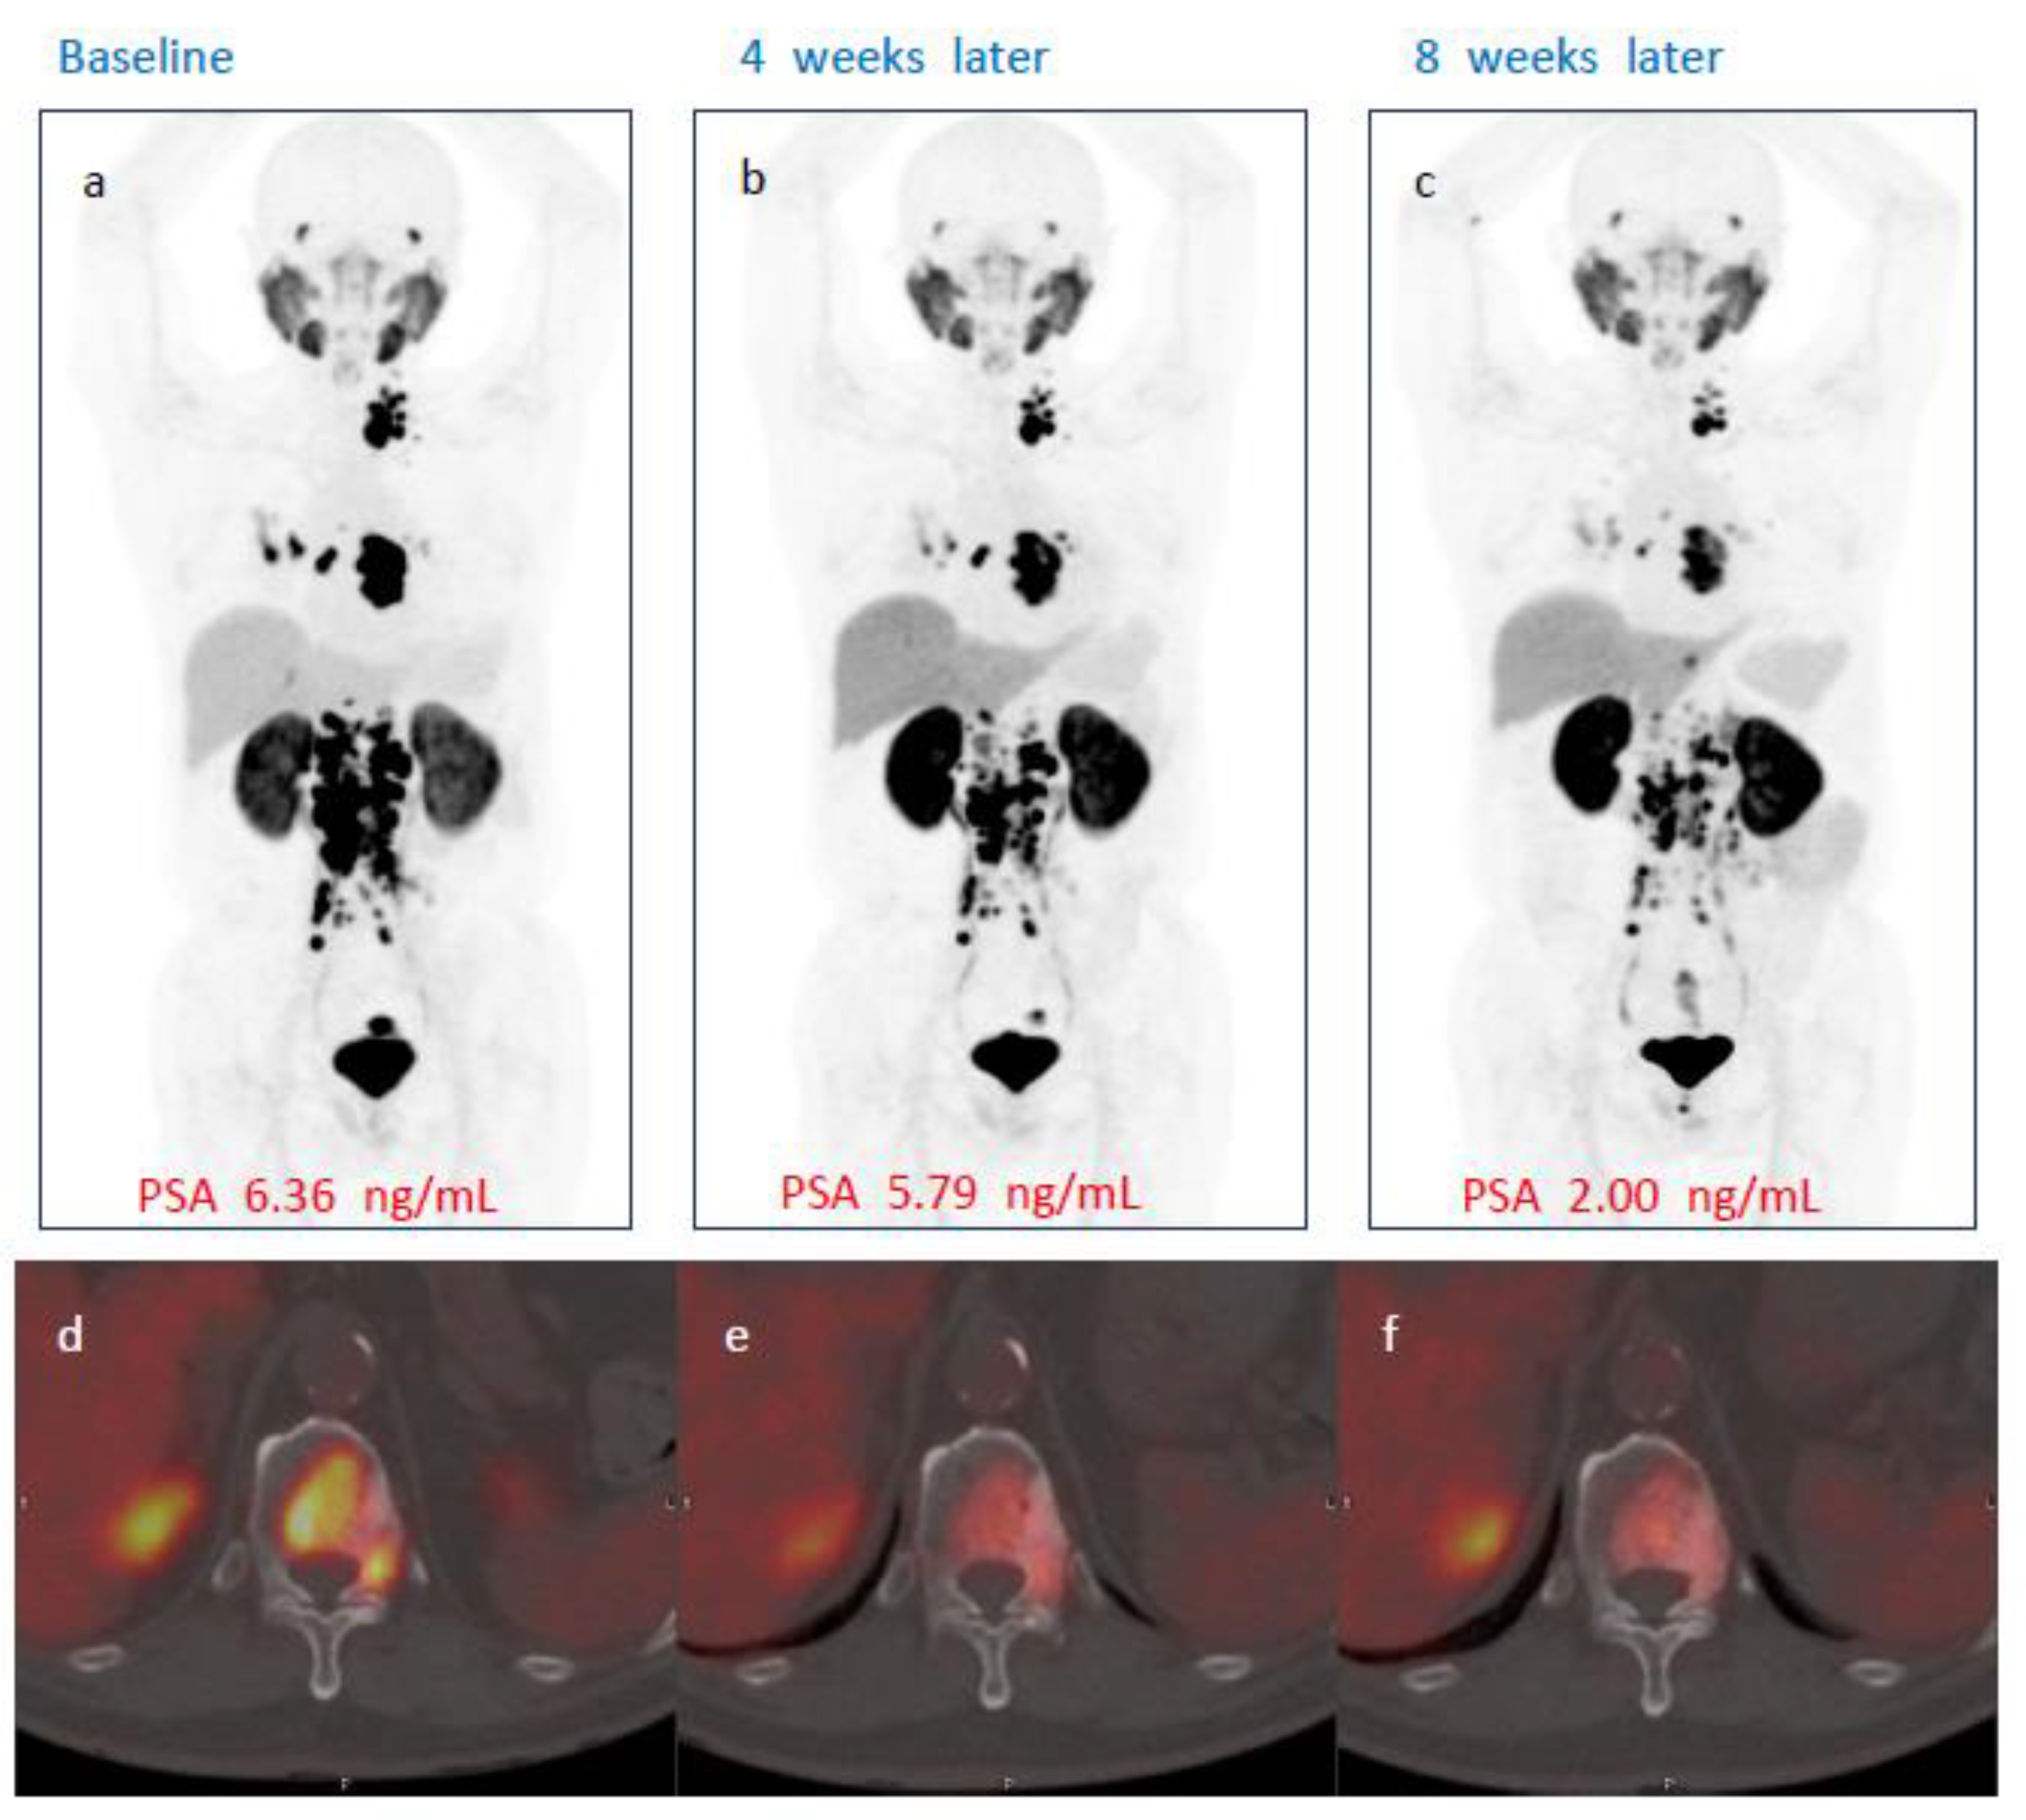

No patient demonstrated complete response on either week 4 or week 8 PSMA PET/CT after single administration of [177Lu]Ludotadipep. However, on week 8 PSMA PET/CT, 14 (56%) subjects had partial response and 10 subjects (40%) had stable disease (SD). One subject demonstrated progression on imaging. The overall objective response rate (ORR) was 40% at week 4 and 56% at week 8. The overall disease control rate (DCR) was 92% at week 4 and 96% at week 8 according to PSMA PET/CT findings. A case of a subject who received 3.7 GBq of [177Lu]Ludotadipep is shown in Figure 3, and another case of a subject who received 4.6 GBq is shown in Figure 4.

Figure 3.

A case of a subject showing PSA response to [177Lu]Ludotadipep. (a,d) Baseline [18F]Florastamin PSMA PET/CT maximum intensity projection (MIP) and fused axial images with multiple bone and lymph node metastases. (b,c) PSMA PET/CT MIP images at four and eight weeks after administration of [177Lu]Ludotadipep showing decreased tumor burden. (e,f) Axial fused PSMA PET/CT images at four and eight weeks show decreased uptake in metastatic lesion in the thoracic vertebra. The patient’s PSA decreased from 6.36 to 2.00 ng/mL at 8 weeks.